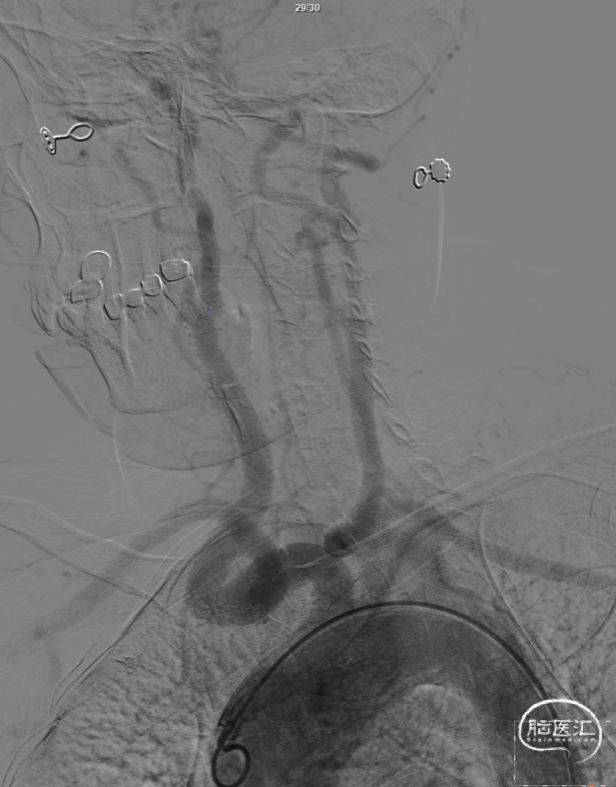

沈阳市第一人民医院柳志一主任医师、孙延宝带来一例右侧大脑中动脉M1段狭窄血管成形治疗病例分享,以下为您精彩呈现。

该病例为右侧大脑半球缺血性卒中,入院后完善头DWI及MRA评估后,提示右侧大脑中动脉狭窄,为此次责任血管,完善脑血管造影,评估血管狭窄情况,给予血管成形治疗。

2.造影提示右侧颈动脉走行迂曲,需通路高到位,为后续导丝着路及球囊送达病变处提供良好支撑。

患者为老年女性,此次急性脑梗死入院,入院后完善头MRA提示右侧大脑中动脉M1段重度狭窄,为此次责任血管,患者既往有右侧半球脑梗死病史,严格内科服药,仍有血栓形成,有介入血管成形治疗指征。

造影提示右侧大脑中动脉M1重度狭窄,双侧大脑前动脉共干,起自右侧颈内动脉,若球囊扩张后释放支架,能覆盖右侧大脑前动脉及颞干,增加缺血事件发生,手术策略上选取单纯球囊扩张成形,同时为扩张后降低夹层发生率,选取小球囊,低压、半顺应性球囊。